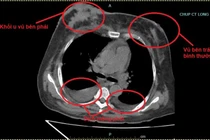

U nguyên bào nuôi là một bệnh lý ác tính của tế bào lá nuôi, gây ra nhiều biến chứng nguy hiểm như băng huyết, nhiễm trùng, suy kiệt, thậm chí diễn tiến thành ung thư nguyên bào nuôi và di căn đến phổi, não, gan....